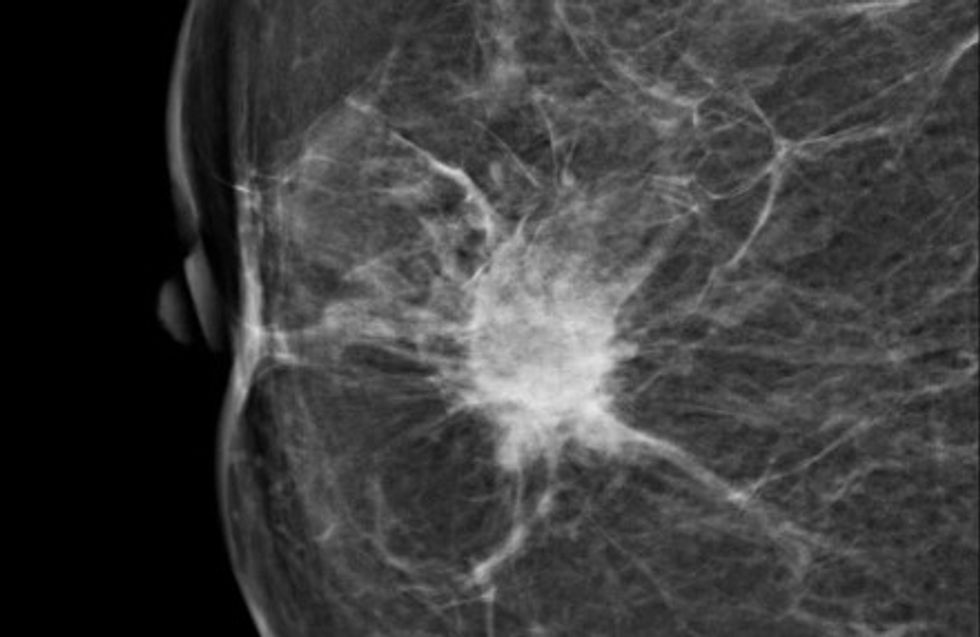

Spiculated Density:

This little bugger can really have you in the corner chewing your nails off. This was one of the findings on my mammogram last year. On a follow-up mammogram the darn thing performed a full disappearing act, not that I'm complaining. But... spiculated... that doesn't even sound like it belongs in my body and where in the world did it go? (I'm hearing Where in the World is Carmen San Diego now) .